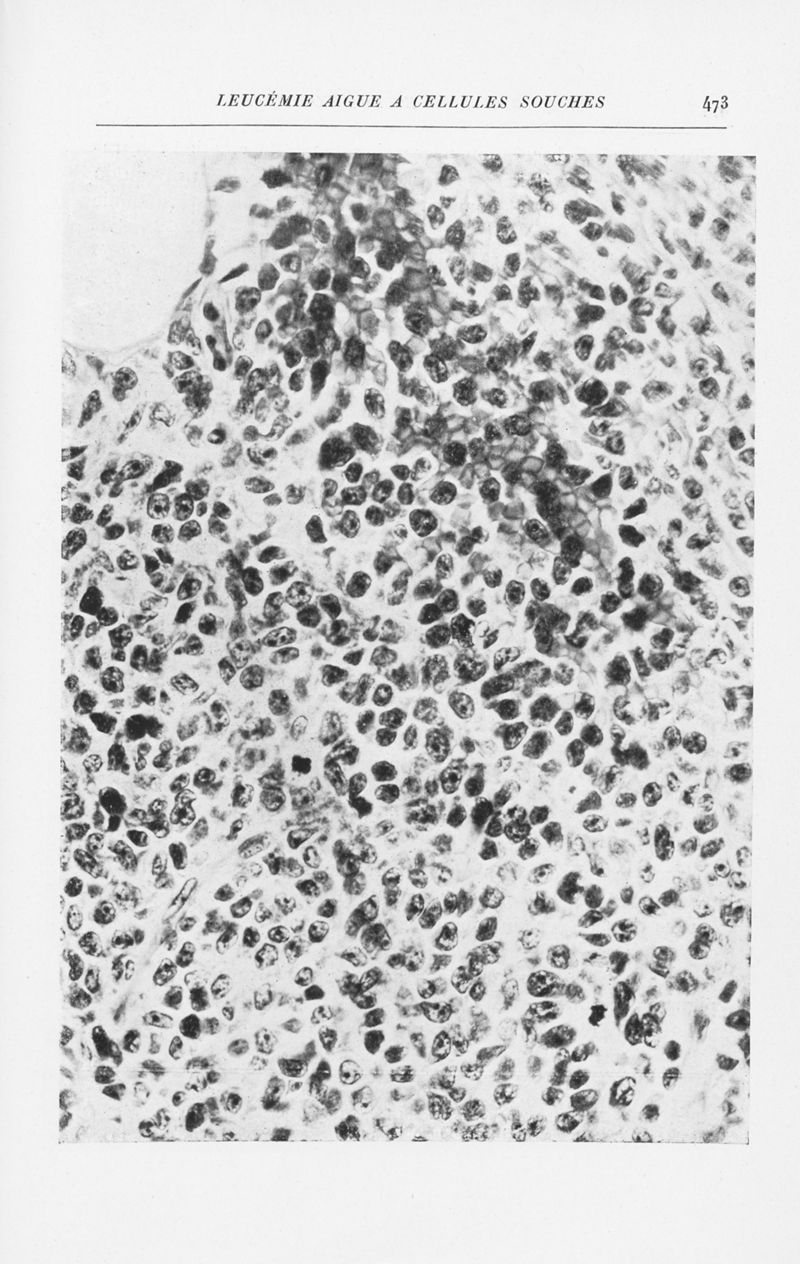

Annales de dermatologie et de syphiligraphie

7ème série, tome X. - Paris : Masson, 1939-1940.